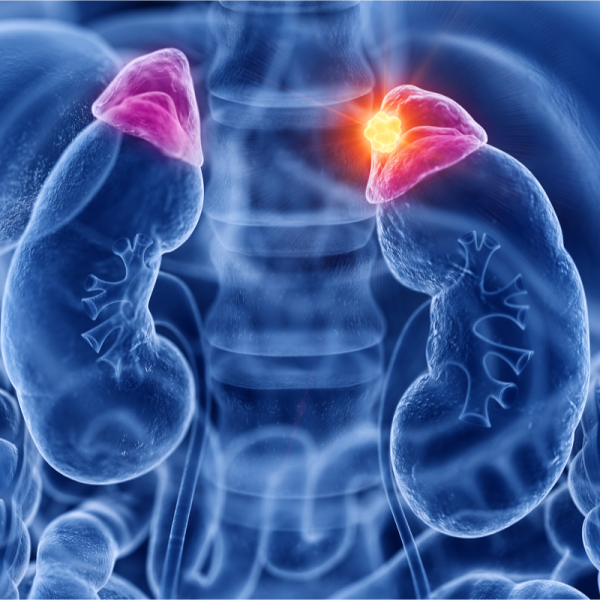

Virsnieru garozas vēzis